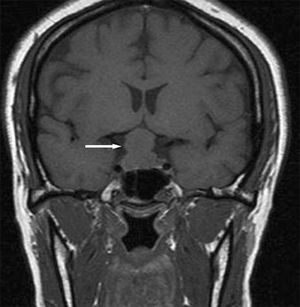

For 3 days, a 28-year-old woman with a history of polymyositis and possible dermatomyositis had fever, chills, and nonproductive cough. She complained of rash, joint pain, and progressive immobility because of severe muscle weakness. For the past 6 years, she had been taking prednisone (60 mg/d), hydroxychloroquine (200 mg bid), and tramadol (100 mg q6h prn for pain).